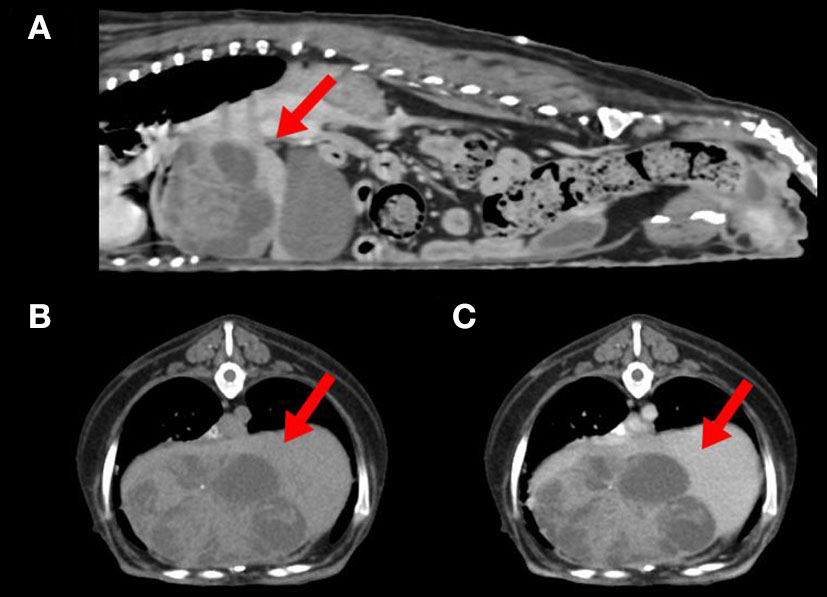

Abdominal radiographic examination showed hepatomegaly and resultant caudally deviated gastric axis. Abdominal ultrasonography showed a multicystic mass at the liver, which was suspected to originate from the left medial or right medial lobe. Computed tomography (CT) identified a left medial liver lobe multicystic mass measuring 7.4 × 4.8 × 4.9 cm, showing adhesions with the diaphragm, caudal vena cava, right medial lobe, and quadrate lobe (Figure 1). In addition, an enlarged pituitary gland and bilateral enlarged adrenal glands were detected. The abovementioned imaging modalities did not show evidence of metastasis to the thoracic or abdominal organs.

Figure 1

Computed tomography of a dog with combined hepatocellular-cholangiocarcinoma. (A) Sagittal view showing a left medial liver lobe multicystic mass (arrow) with adhesion to diaphragm and caudal vena cava. (B) Plain and (C) postcontrast axial view of the cranial abdominal region showing a hypoattenuated liver mass (arrows) with minimal contrast enhancement.